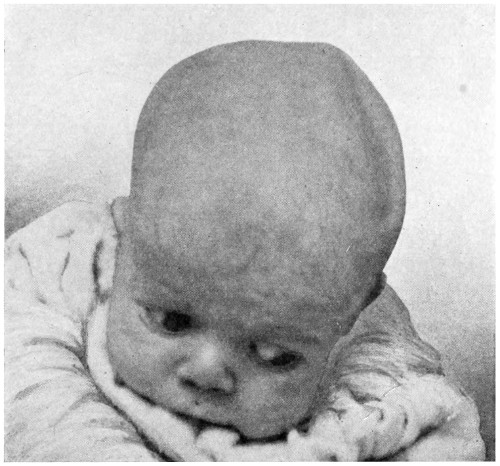

| 21. A cephalocele over the anterior fontanelle | 35 |

Fig. 21. A Cephalocele over the Anterior Fontanelle.

(For further description, see text.)

3. More rarely, the tumour overlies the anterior or posterior fontanelle. A case of this nature is depicted in Fig. 21, the tumour, situated over the anterior fontanelle, bulging over the temporal and frontal regions to a remarkable extent.

Sincipital cephaloceles are usually quite small, but the occipital variety and those situated in[35] the region of the anterior fontanelle frequently attain a great size (see Figs. 20-22).